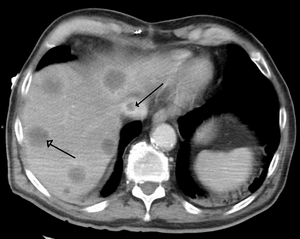

Budd–Chiari syndrome secondary to cancer; note clot in the inferior vena cava and the metastasis in the liver